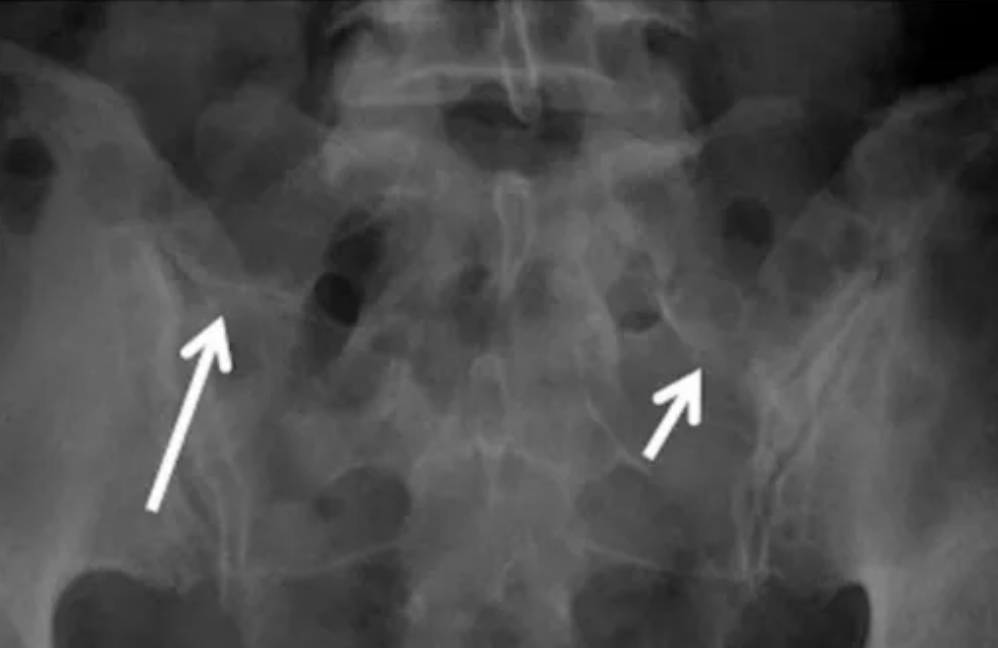

IIa型:单侧横突与骶骨形成假关节伴硬化,但未融合

(白箭指向假关节,但很难清晰显示)